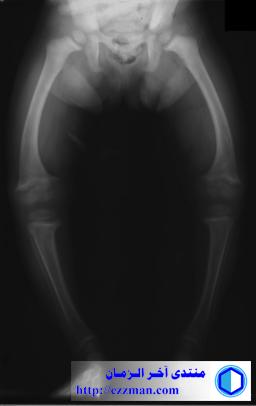

التشوه التدويري (Rotatory deformity) عند الانسان دليل على وجود مشاكل في العظام. وهذا التقوس ناتج تلين العظام (Osteomalacia) الذي يصيب البالغين، أما ما يصيب الاطفال يسمى كساح (Ricketsومن أهم أسباب هذا التشوه نقص فيتامين دال أو الكالسيوم أو الفوسفور.

اشعة توضح تقوس الساقين و الفخذين